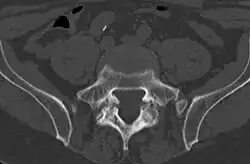

Computed tomography

Cross-sectional image of a vertebra showing spondylolysis.

Commonly known as a CT Scan or CAT scan, this form of imaging uses x-rays to produce multiple cross-sectional images, or "slices", through a part of the body. This allows a physician to evaluate the body in greater detail than an x-ray allows. For this reason the CT scan is much more accurate in detecting spondylolysis than an x-ray. Bone scintigraphy combined with CT scan is considered the reference standard, which means that it is best at detecting spondylolysis.[16][18]